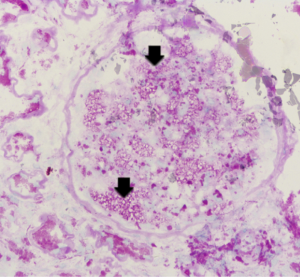

Pathological results of renal biopsy

Renal biopsy results from the proband (III7) revealed vague vacuolization of podocytes on microscopic examination after staining by periodic acid-Schiff (PAS) (Figure 2). Section lining epithelial cell proliferation and wall segment thickening were also observed. The renal tubular epithelial cells showed granular, vacuolar, and foamy changes (Figure 3). There was an infiltration of renal interstitial inflammatory cells, severely fibrosis, and internal renal artery wall thickening.

Electron microscopy revealed obvious vacuolar degeneration of capillary endothelial cells, typical electron-dense multilamellar inclusions and zebra bodies and an increase in secondary lysosomes in the cytoplasm of epithelial cells (Figure 4).

This report shows an important point regarding kidney biopsy. The kidney is one of the main target organs of FD, and renal pathological examination has been widely carried out. Although the proband’s kidney specimen demonstrated a mildly abnormal appearance under light microscopy examination, electron microscopy clearly demonstrated lamellated myelin structures and confirmed the diagnosis of typical FD (26). If the characteristic changes of renal pathology can be fully understood, when they are combined with clinical multisystem performance, the diagnosis rate of FD can be greatly improved. Some clinically normal heterozygous females have typical kidney biopsy findings (27). GLA activity when measured in blood may not reflect the true level of the enzyme activity in the affected organs. Therefore the critical threshold of GLA activity is hard to be determined (28). This implies that biopsy of the involved organ could help us identify the extent of FD and start therapy accordingly.